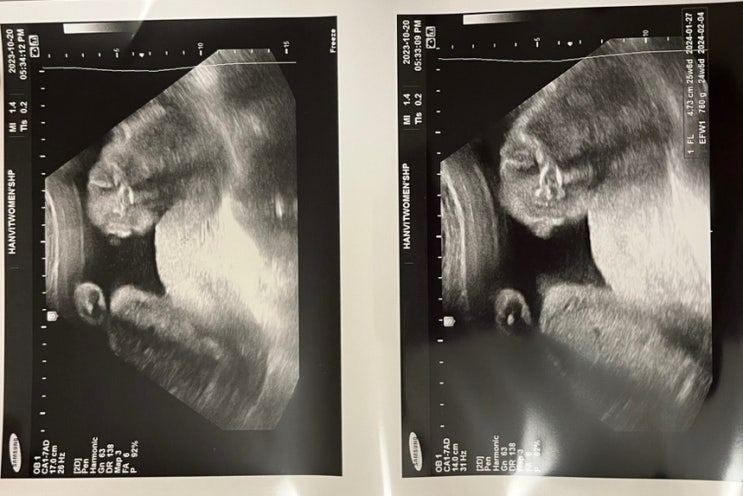

임신7개월 25주 일상 _ 철분제 복용시작 + 입덧약 줄이기

25주를 맞이한 모찌? 시간이 어떻게가는지모르겠는 요즘. D-100 파워 J는 마음이 급하다. 뭐 빠진거없...

임신7개월 24주 일상 _ 정기검진 / 베이비페어 / 아기용품 구매

임신 7개월 입성✌️ 24주 일상? 이번주차엔 산부인과 정기검진이 기다리고있다. 이때부턴 조산을 조심...